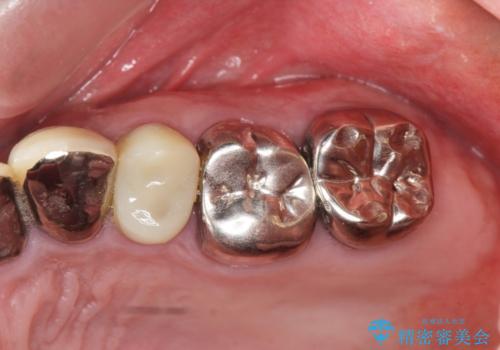

銀歯を外し、インプラントを入れたい

- 「治療途中の歯を治したい。この際、銀歯も全て外したい。インプラントも入れてしっかり噛めるようにしたい。徹底的に歯の治療をしたい。」

と総合的な治療を希望され来院されました。

ここの歯の状態を精密に検査し、根管治療、セラミック治療、インプラント治療を含む総合的な歯科治療を計画します。